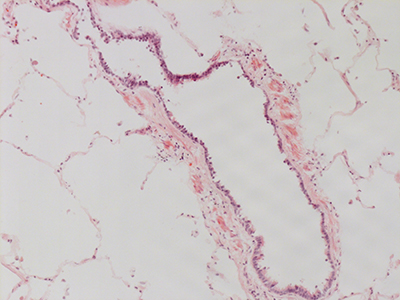

31 Year Old Adult Human Lung D0036 H&E